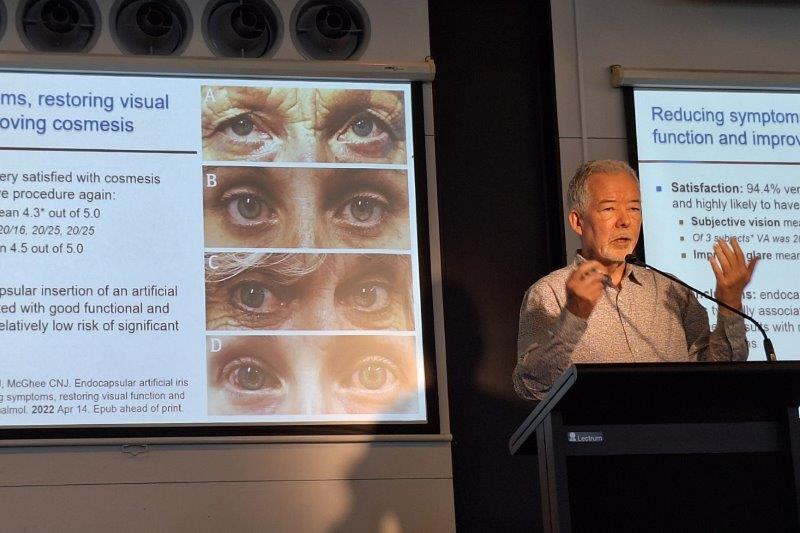

For patients with advanced-stage disease whose photoreceptors are no longer viable, but who still have functioning inner retinal cells (Fig 5), optogenetic therapy represents a mutation-independent strategy. This approach involves introducing light-sensitive proteins (opsins) into surviving retinal cells, such as ganglion or bipolar cells, thereby restoring light responsiveness (Fig 6). Early clinical trials have demonstrated the potential for partial restoration of light perception and basic visual function11. They have also shown some significant functional outcomes in cases of advanced retinitis pigmentosa. We are also commencing a clinical trial (Abacus-2) with KIO-301 (Kiora Pharmaceuticals) in Auckland in the next few months.